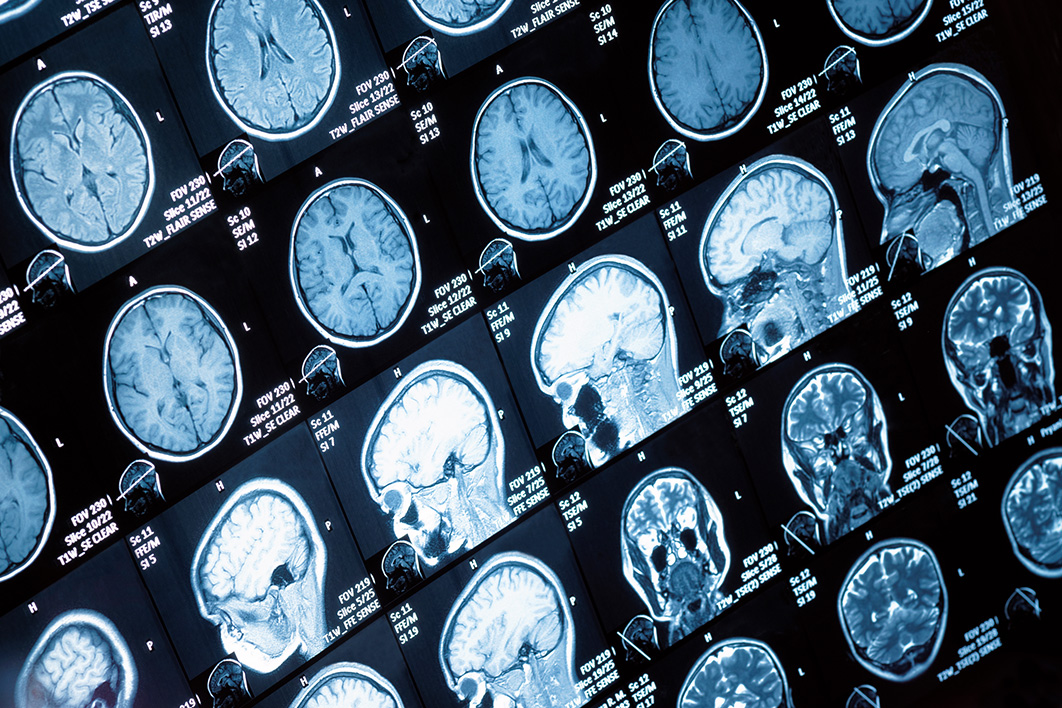

A whole lot of people think that AI is going to eliminate many human jobs. Perhaps no one is more confident of this prediction than the engineers who are actually building the AI in question. For example, nine years ago, Geoffrey Hinton — one of the key creators…